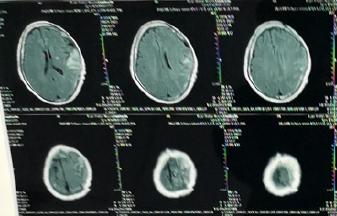

伤后8天复查头颅CT及MRI:提示左基底节区急性腔隙性脑梗死(2018-10-04):由于10-03晚上出现右侧肌力下降,不能言语

(1)新鲜与陈旧性脑梗死的鉴别:新发生的脑一般认为24小时内CT扫描多不能清楚显示。陈旧性脑梗塞往往在伤后首次头部CT扫描即可清楚显示,密度低,边界清楚。

(2)外伤性与病理性脑梗死的鉴别:外伤性脑梗塞常伴发于严重的颅脑外伤,多单发;病理性脑梗塞常见于老年人,既往有脑血管疾病史,无明确的头部外伤史或外伤轻微,常多发,以腔隙性脑梗塞多见。

4、经过脑CT和MRI或脑血管造影检查证实有脑梗死灶

2、诊断:影像学检查(CT或者MRI)是诊断脑梗塞的依据